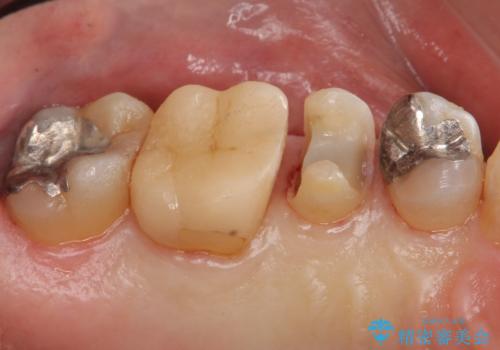

銀歯の下が虫歯 セラミックインレーに

- 銀歯の下が虫歯になっていたため、虫歯を取り、セラミックインレーで修復しました。

見るだけでは、わかりにくいのでしっかりレントゲンを診てもらえるような定期検診が大事です。

銀歯が合っていないなどは、見た目だけではわかりにくいことがあります。

早めに見つけて、症状が出る前に治すことが大事です。

歯科医師にレントゲンをしっかり診てもらうことが重要です。